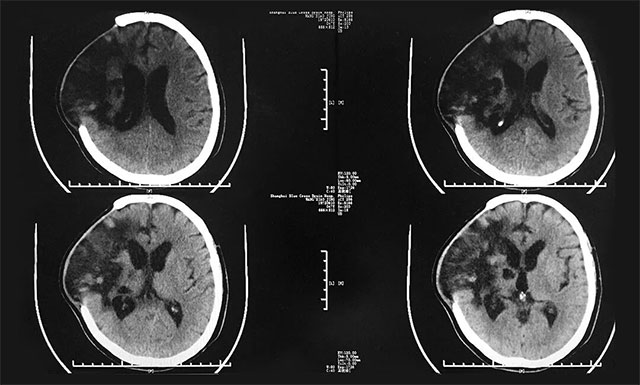

▲ 入院前,患者腦部感染嚴重

入院后,潘仁龍主任對患者進行了全面而細致的檢查,并針對其之前腦出血的情況予以營養(yǎng)神經(jīng)、改善微循環(huán)、促醒、抗感染、補液等對癥治療;同時,還邀請康復科專家、高壓氧科專家及中醫(yī)科專家分別進行會診,并給予相應(yīng)輔助治療,之后患者情況較前有所好轉(zhuǎn),GCS評分也從之前5分變?yōu)?分(E4分、V1分、M3分)。